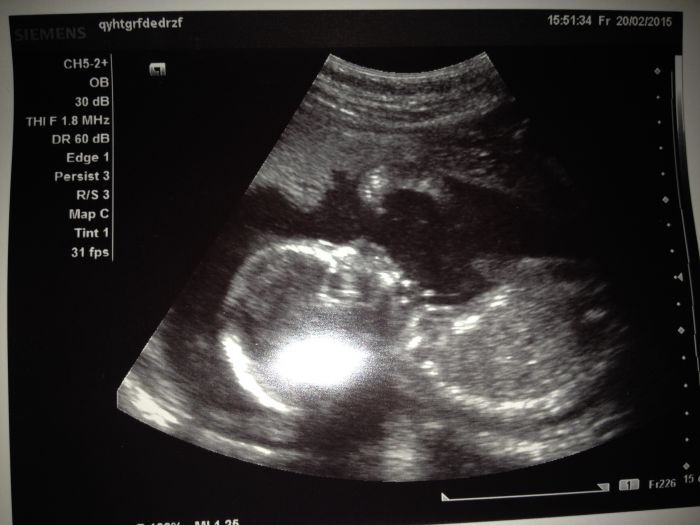

Ahojky holky,byla jsem tu naposledy pred měsícem, tak jsem se prisla mrknout co nového. Jinak ted jsem 21+5 tt a uz cítím docela dobre kopanecky:)krasnej pocit. Uz mame i pravidelný intervaly, tak se vždy těším na určitou hodinu a čekám :). Na velkém utz jsem uz take byla, akorat me trošičku postrasili, ze na miminko neco na srdicku(focus) a musím ted 14 dni čekat na výsledky a pak se uvidí:( nemáte s tím nějaká zkušenost? Nevim co od toho čekat...jsem docela vyplasena:(..dělohu mam take porad pod pupkem a to jsem 22 tt. Tak snad bude vse ok. Zavolám nějaké fotecky miminka:)

jé, krásná fotečka :)